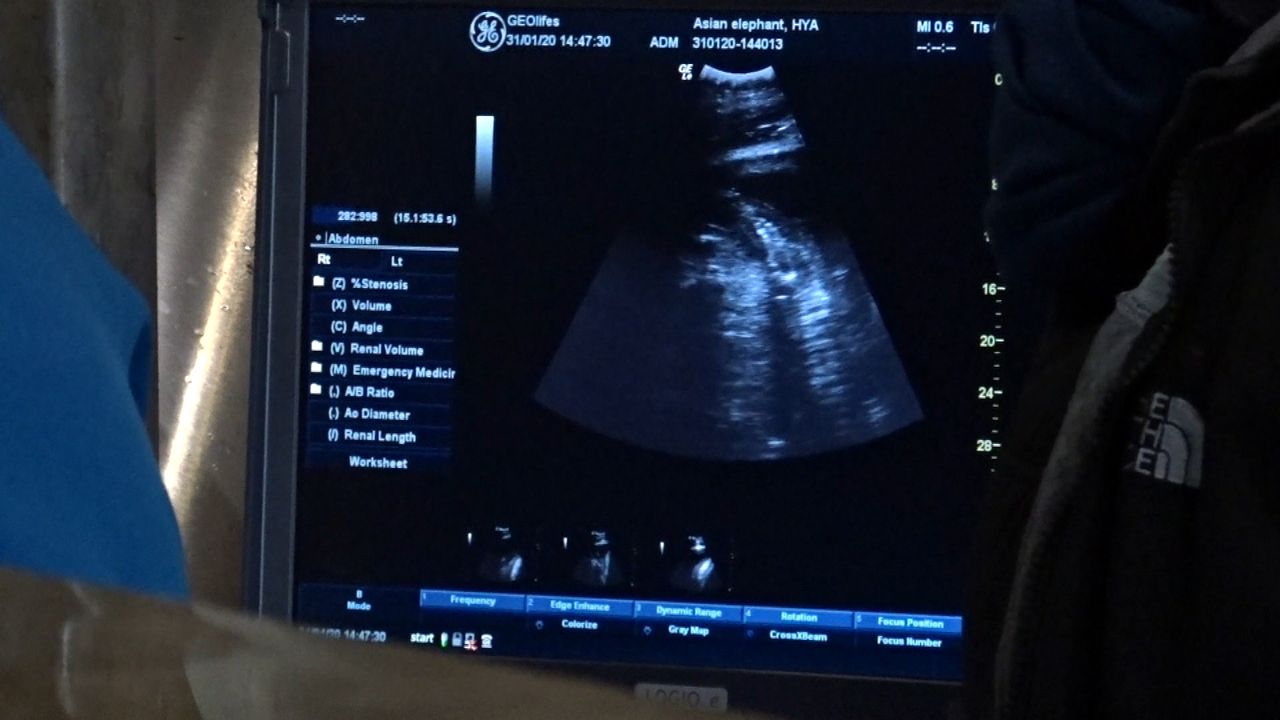

De bevalling is dus niet te plannen. Het olifantje kan er opeens zijn. Maar het kan ook nog tot december duren. Een olifantenmoeder is gemiddeld 22 maanden zwanger. Pas na een jaar is de dikke buik ook daadwerkelijk te zien.